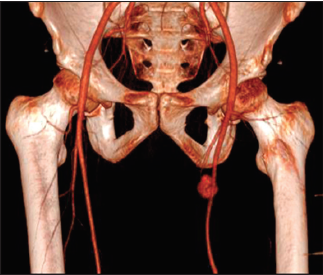

Héctor Hugo Romero-Garza, Alan Fuentes-Ortiz, Rogelio Salinas-Dominguez, Gerardo Enrique Muñoz-Maldonado

|

|

|